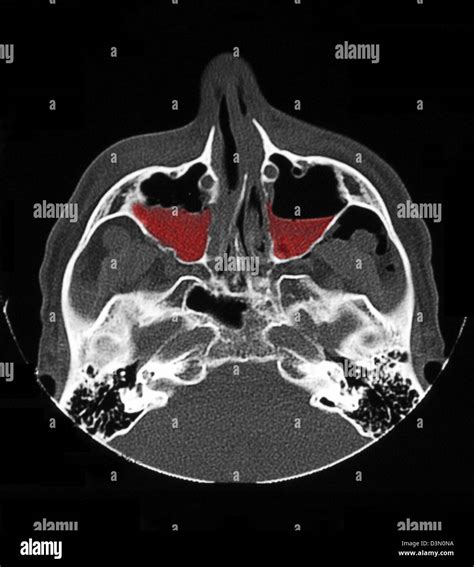

Since these cysts rarely present with overt symptoms, diagnosis is almost always achieved through imaging. When your dentist or ENT specialist identifies a potential Cyst Sinus Maxillaris, they will use advanced imaging technology to differentiate it from other, more serious pathologies.

Imaging Method Purpose in Diagnosis

Panoramic Radiograph (OPG) Provides a broad view; often the first imaging modality where a cyst is spotted.

Cone Beam CT (CBCT) Offers a 3D view; essential for accurately measuring the size and location of the cyst.

MRI Used in complex cases to determine the nature of the fluid content within the cyst.